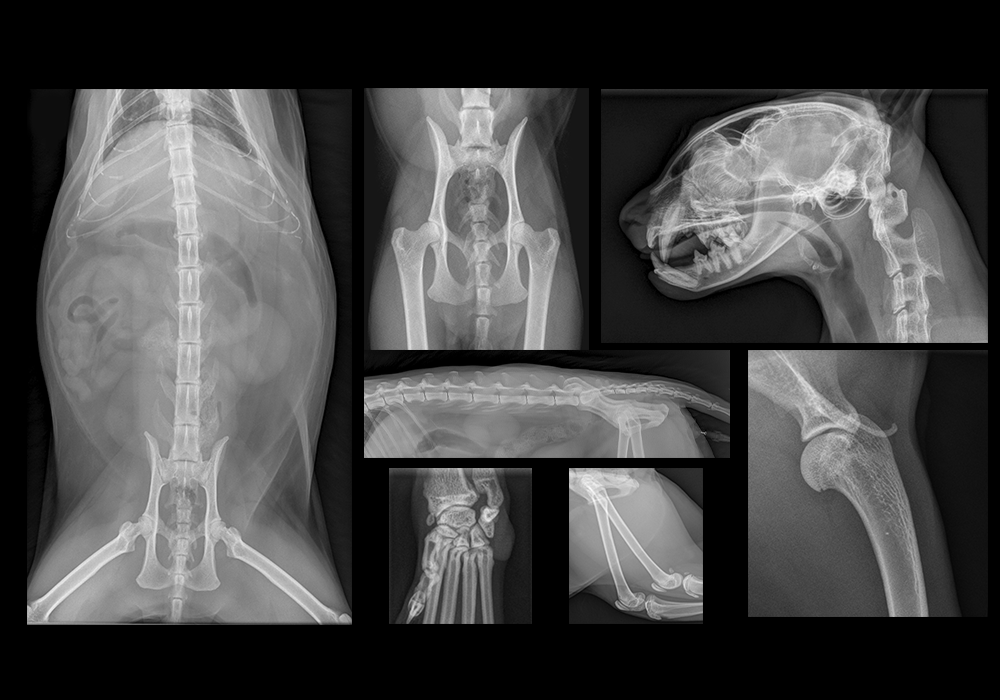

Рентген у кошки

Рентгенологическое обследование кошки является диагностической процедурой, которая использует рентген-лучи для получения изображений внутренних органов и тканей животного. Безопасный и неинвазивный метод используется для:

• диагностики травм, позволяя ветеринару оценить состояние костей;

• обнаружения заболеваний;

• оценки состояния органов;

• оценки роста и развития питомца.

Что показывает рентген

Диагностическая процедура позволяет обнаружить заболевания, первые симптомы которых невозможно выявить во время первичного визуального осмотра.

Патологии и заболевания, которые можно обнаружить с помощью рентгенологического обследования:

Виды рентген-исследований

Виды рентгеновских исследований, которые могут быть проведены у кошки:

1. Дентальный. Исследование зубов и структур около них. Обязательно назначается при необходимости исправления прикуса, проведения имплантации, лечении и удалении зубов.

2. Рентген лап. Лучевая кость на передних лапах, бедренная на задних — самые уязвимые места у кошек. Обследование рекомендуется при обнаружении признаков дисплазии суставов, подозрении на переломы, вывихи, новообразования.

3. Рентген легких и трахеи. Обследование позволяет оценить работу легких, дыхательных путей, трахеи, обнаружить инфекции, пневмонию, бронхит, наличие инородных тел.

4. Рентген позвоночника. Исследование состояния позвоночника, спинного мозга. Назначается в случае травмы, неврологических симптомов, подозрении на прогрессирование дегенеративных заболеваний суставов.

5. Рентген с контрастным веществом. Введение контраста повышает точность диагностики внутренних органов, позволяет обнаружить аномальные процессы, выявить особенности анатомического строения. Снимки делают 2 раза — без контрастного вещества и после его введения. Подходит для диагностики заболеваний органов ЖКТ, мочевого пузыря, кровеносных сосудов.